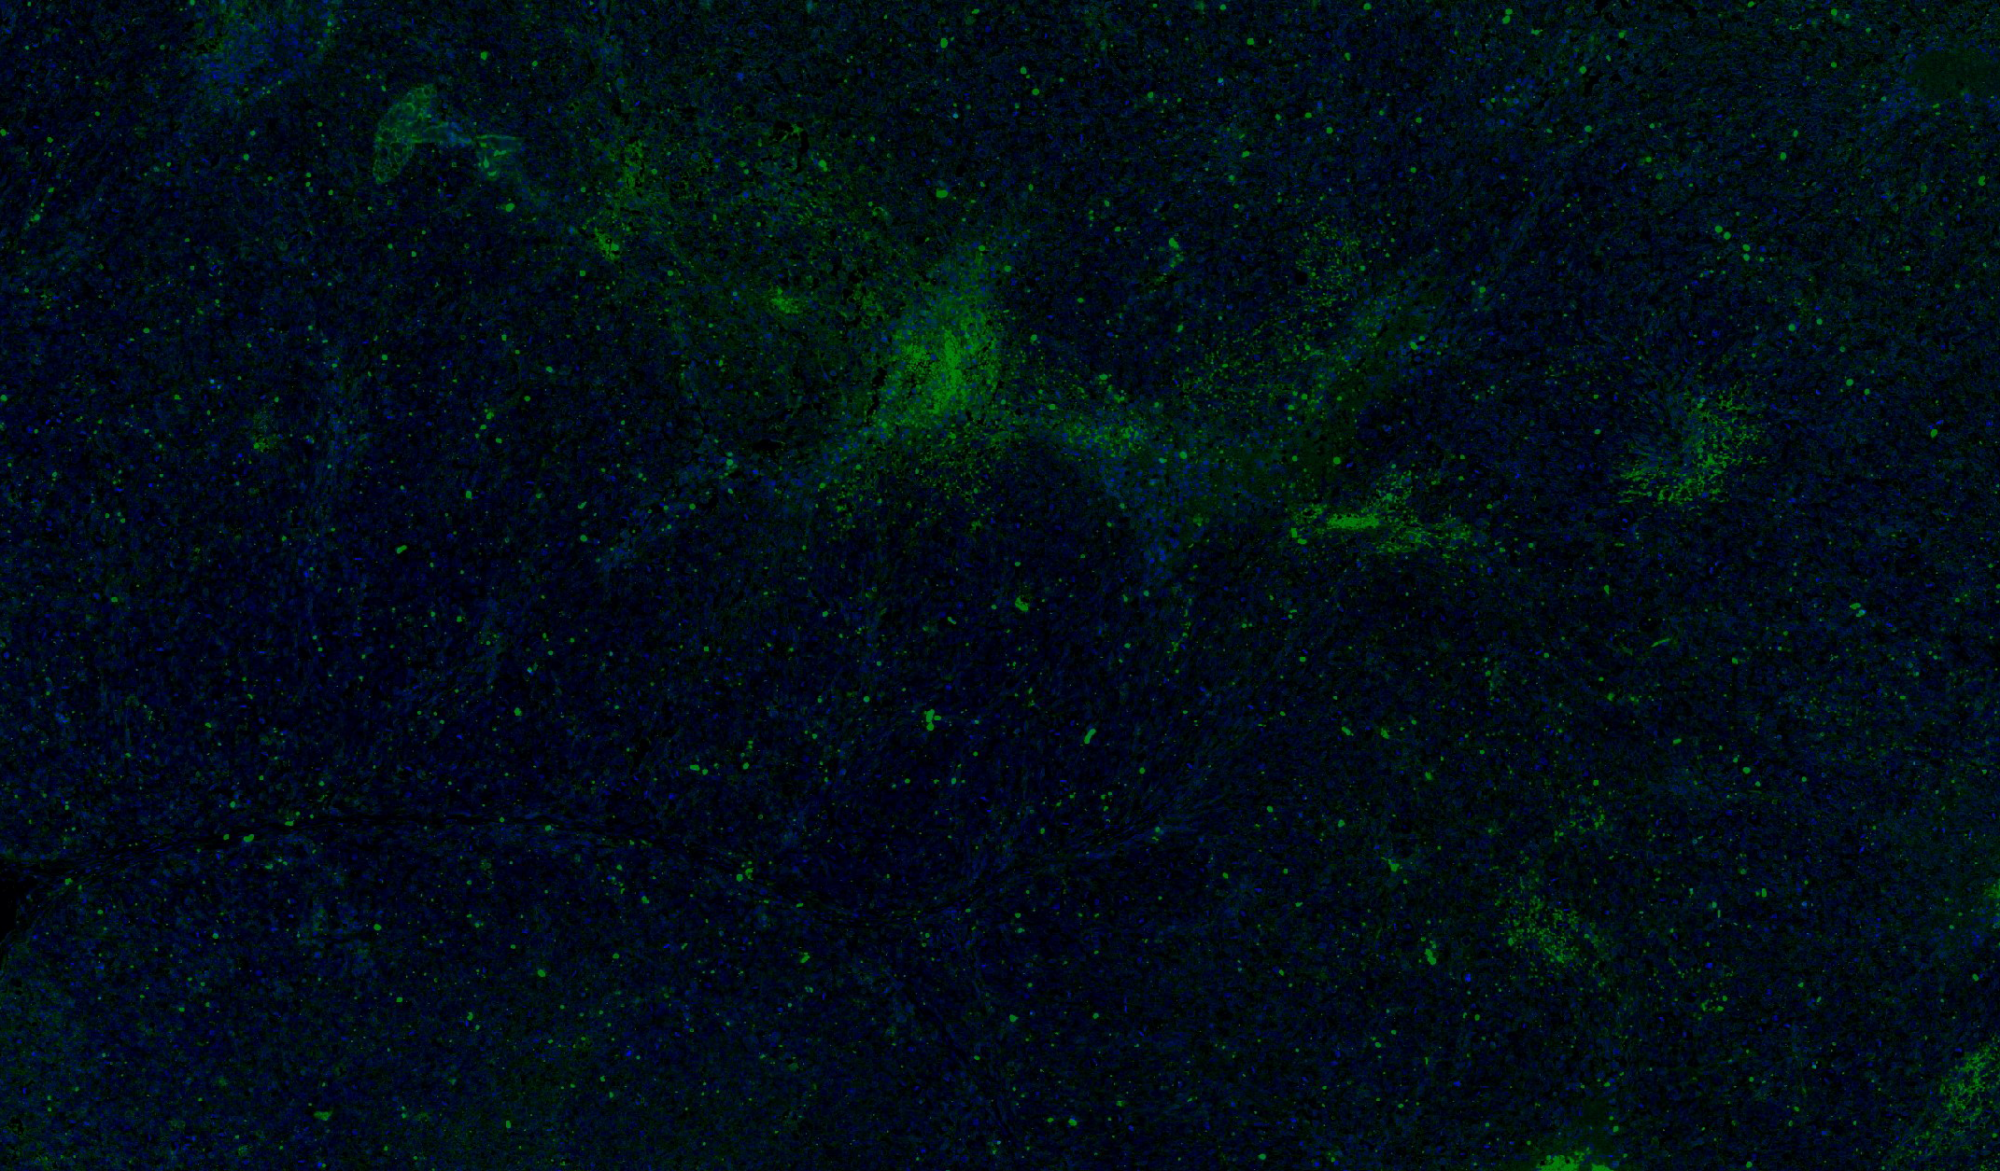

病理平臺(tái)可承接:石蠟切片,切片掃描,熒光掃描,HE染色,各種特殊染色,如:Masson、油紅O、PAS、番紅O、ALP、TRAP、甲苯胺藍(lán)以及免疫組化/熒光、原位雜交等,3D HISTECH滿足對(duì)結(jié)果高質(zhì)量,高標(biāo)準(zhǔn),周期快的實(shí)驗(yàn)外包需求,并提供染色培訓(xùn)服務(wù),分線上視頻,線下實(shí)操帶教兩種培訓(xùn)方案。

案例展示